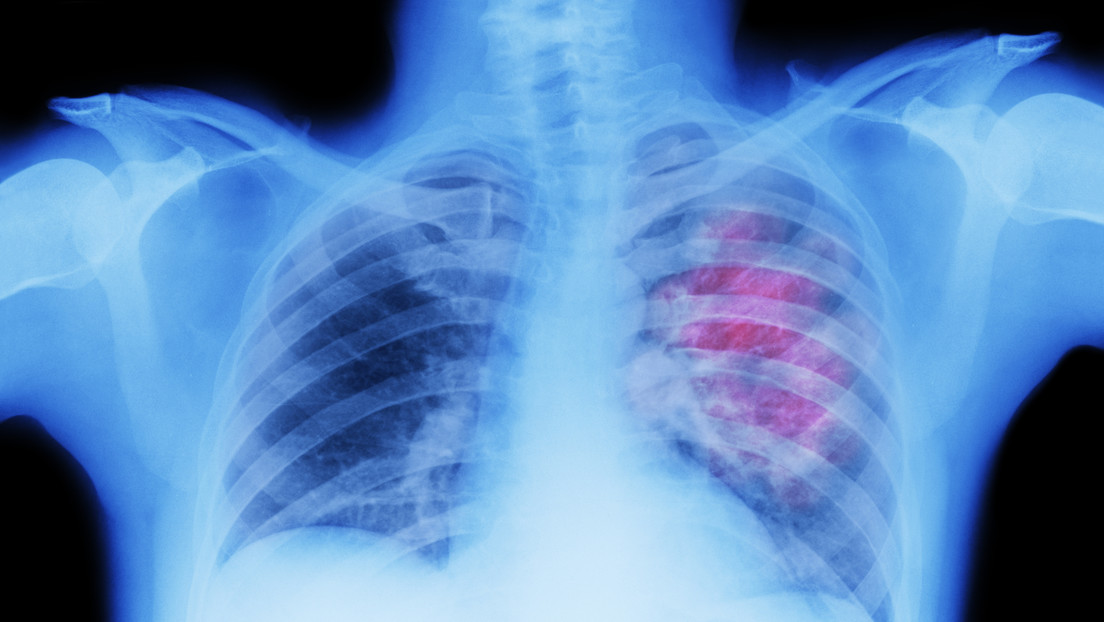

El linfoma no Hodgkin es un tipo se cáncer que se origina en los glóbulos blancos y afecta el sistema linfático, que forma parte del sistema inmunitario del cuerpo, detalla la Sociedad Americana contra el Cáncer.

Esta enfermedad es más común entre las personas mayores de 60 años. Según su extensión y el subtipo del cáncer, la tasa de supervivencia a 5 años varía del 64 % al 84 %, informa la Sociedad Americana de Oncología Clínica.